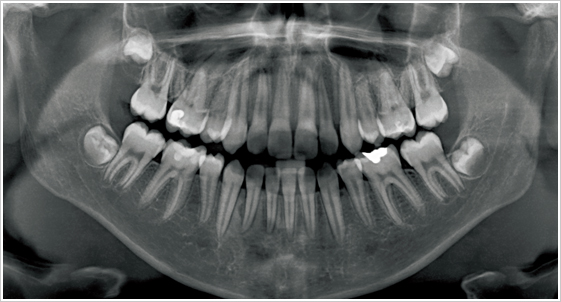

3D電腦斷層精確定位系統 與 2D環繞式全口X光片的差別

2D影像是有立體空間限制的,將立體影像壓縮為平面來呈現,除了變形的因素外只能提高牙床的高度與寬度的判讀,而無法提供牙床厚度的判讀;故醫師時常無法由2D影像判斷舌側夾側(牙床厚度)的距離及角度。

往往從2D判斷 surgical stent(手術定位板)的位置是正確的,但是事實上透過3D立體影像的診斷,發現原本以平面影像預測的種植方向過偏,在手術前及時修正手術定位板的角度及位置,並事先做好正確的治療計畫,才能提高植牙的成功率與準確度,更能增加植牙後牙齒形態的美觀!沒有精準的儀器協助專業醫師進行手術,往往造成醫療診斷上的不精確,甚至疏失!患者相對也會失去信心,甚至失去了治療的黃金時機。

隨著3D科技植牙的發展,植牙的手術已經越來越精準與安全。除此之外,對疼痛的控制與傷口的微創方面更是細心要求;如果可以在缺牙的第一時間得到妥善的醫療診治更可以節省不少時間與金錢。

精準安全的3D科技植牙

拍攝口腔3D斷層,能讓醫生更準確的知道每位患者牙齒的實際狀況,牙科診斷用的X光劑量,會引起罹患疾病的可能性極低,會產生癌症的機率更是微乎其微。在手術前提早做治療規劃及植牙精確定位,不但提高植牙的成功率與準確度,更能增加術後牙齒的美觀與咬合的長久穩定,讓患者享有更好的醫療成果。